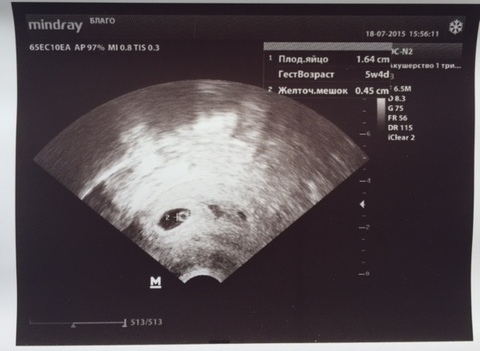

Вчера был первое УЗИ(5-6 акушерская неделя),до этого дня даже и не думала об этом. Только перед самим посещением почувствовало маленькое переживание, но со мной был муж, который конечно же, пытался меня настраивать позитивно, во чтобы то не стало.

Однозначно ехала к доктору, для убеждения что беременность в маточная и всё) Но, к сожалению, немного мое здоровье подвело.И Рядом с малышом обнаружилась маленькая отслоечка.... Сначала шок от устрашающего слова, страх, ступор.... Ну а потом, как-то разом пришла в чувства и стала думать позитивно. В этой жизни все лечиться, и конечно, переживать не стоит, ибо это только во вред пойдет.

Прикладываю первый снимок ляльки .